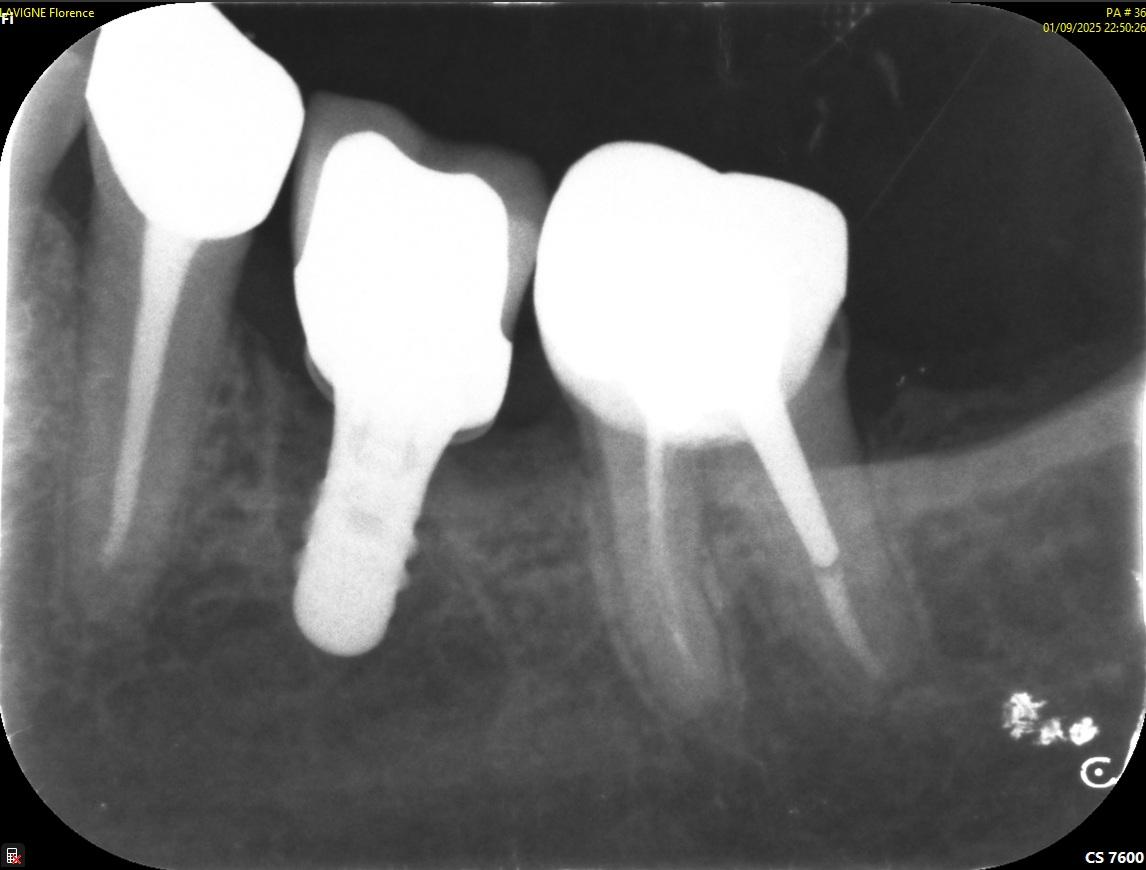

Retro couronne